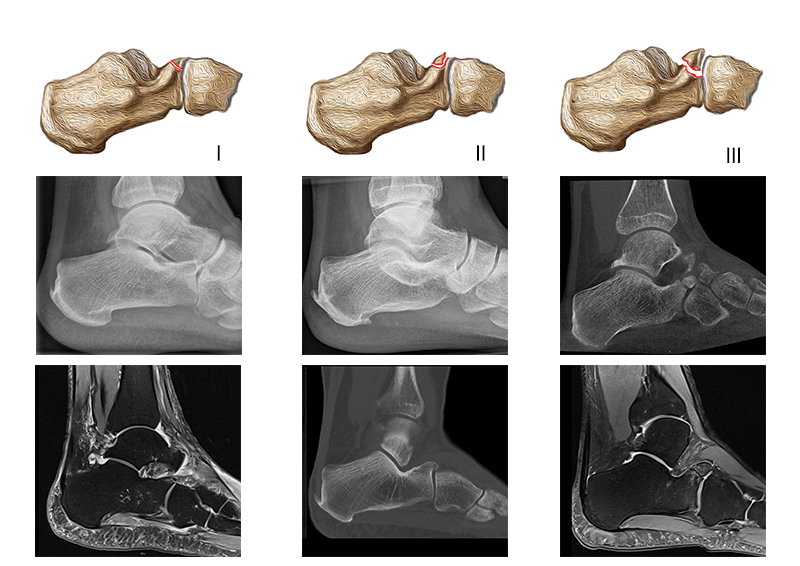

Die Klassifikation der PAC Verletzung erfolgt nach Degan et al. 3. Diese unterscheidet insgesamt drei Fraktur-Typen anhand der Fragment-Größe und der artikulären Beteiligung.

Zum Lesen der Bildbeschreibung und zur Vollansicht bitte das Bild anklicken. Bild: M. Walther

Die Klassifikation nach Degan wurde bereits 1982 publiziert und basiert auf der Auswertung von konventionellen Röntgenaufnahmen von 25 Patienten 3.

Typ I: Nicht-dislozierte, extra-artikuläre Avulsionsfrakturen des Processus anterior.

Typ II: Dislozierte, extra-artikuläre Frakturen des Processus anterior.

Typ III: Große, dislozierte Frakturen mit Affektion des calcaneo-cuboidalen Gelenkes (CC-Gelenk).

Frakturen des Processus anterior calcanei sind in etablierten Kalkaneusfraktur-Klassifikationen (Sanders, Essex-Lopresti, Arbeitsgemeinschaft für Osteosynthesefragen (AO/OTA)) gar nicht oder nur am Rande erwähnt 252627. Diese Klassifikationen subsumieren die Frakturen des PAC unter den extra-artikulären Frakturen. Zwipp und Kollegen führten mit der „Integral Classification of Injuries“ (ICI) eine detaillierte Betrachtung der PAC Frakturen ein. Hier werden diese als artikuläre Verletzungen klassifiziert und zudem begleitende Bandverletzungen und die Fragment-Dislokation berücksichtigt 28. Eine Klassifikation - möglicherweise auf der Basis von CT-Bildern - in die die Fraktur-Lokalisation, die Fragment-Größe und -Dislokation sowie die Begleitverletzungen eingehen, wäre hilfreich, um sich dieser Frakturentität und der damit einhergehenden Behandlungsempfehlung weiter zu nähern. Die von Degan beobachteten extra-artikulären Frakturen im konventionellen Röntgen imponieren in CT und MRT als knöcherne Ausrisse des Lig. bifurcatum im Randbereich des Gelenks. Häufig finden sich aber auch bei kleinen Fragmenten eine intraartikuläre Komponente.